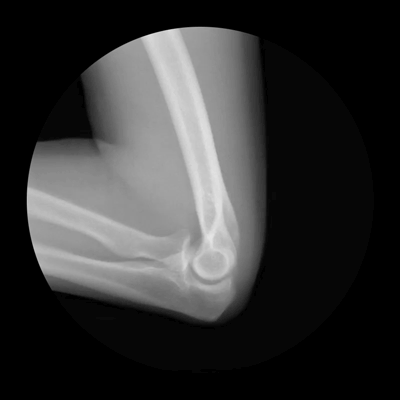

Биомеханика локтевого сустава на рентгене

В локтевом суставе возможны сгибание и разгибание (рис. 6.1). Сгибание происходит под действием передней группы мышц плеча, а именно двуглавой мышцы плеча и плечевой мышцы. Трехглавая мышца плеча обеспечивает разгибание.

Рисунок 6.1. Объем движений предплечья. А. Сгибание и разгибание. Б. Пронация и супинация.